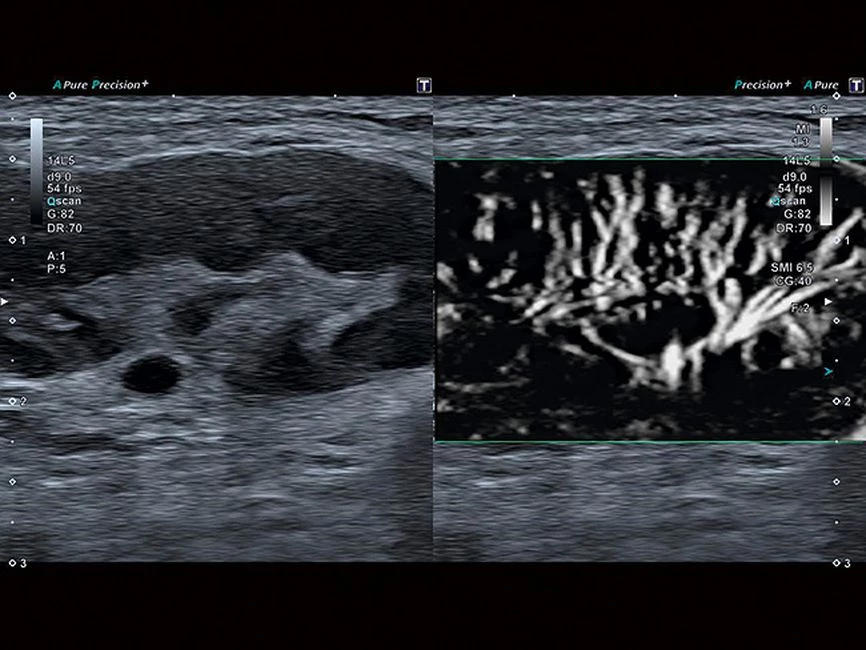

- SMI. Опция, упрощающая визуализацию микроциркуляторного русла. С ее помощью обследуются сосуды с низкой интенсивностью кровотока, изучаются наиболее тонкие структуры. SMI упрощает диагностику новообразований, минимизирует вероятность ошибки.

Уровень сосудистой визуализации SMI в сочетании с высокой частотой кадров повышает диагностическую достоверность при оценке поражений, кист и опухолей.

SMI с цветовой кодировкой позволяет одновременно отображать информацию о потоках и оттенках серого с высокой временной и пространственной информацией.